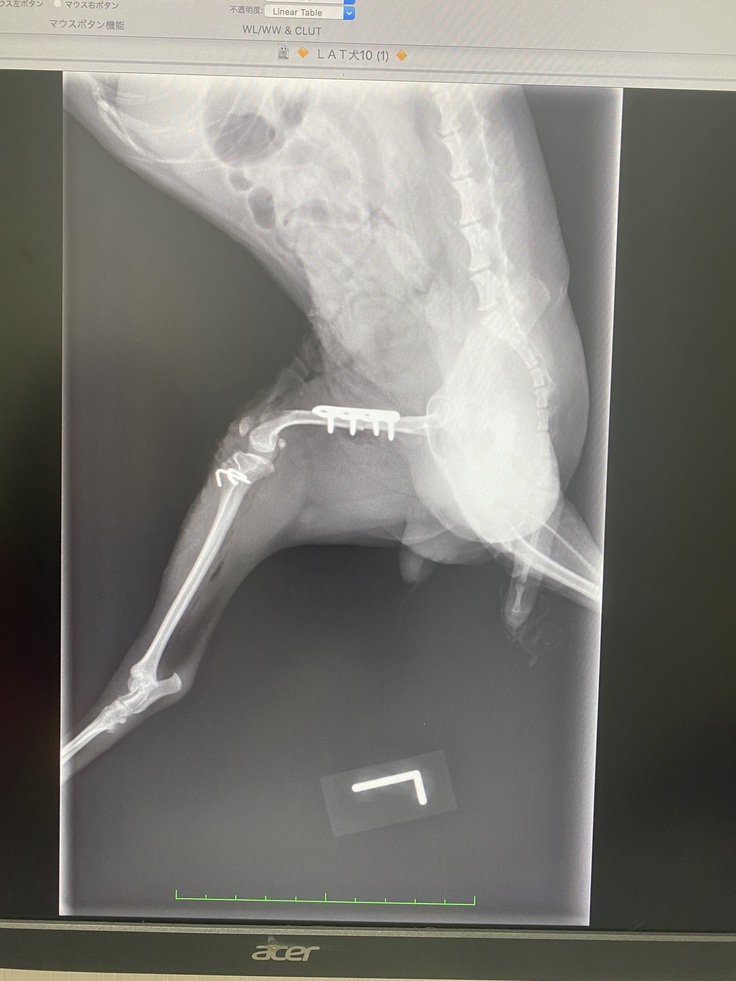

手術後のレントゲン写真

手術後のレントゲン写真です。

大腿骨部分切除したところを固定してるピンと別に、骨が細すぎるからとワイヤーでも固定してもらってます。